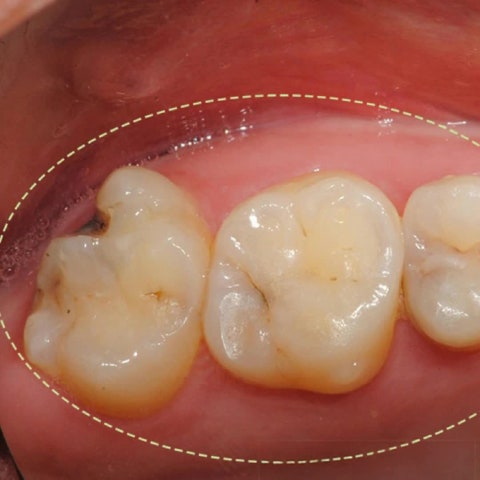

그리고 근래에 개원한 치과중에 드물게 임상경력이 20년차이며, 치아교정뿐 아니라 임플란트,

충치치료등 전반적인 진료를 모두하고 있습니다.